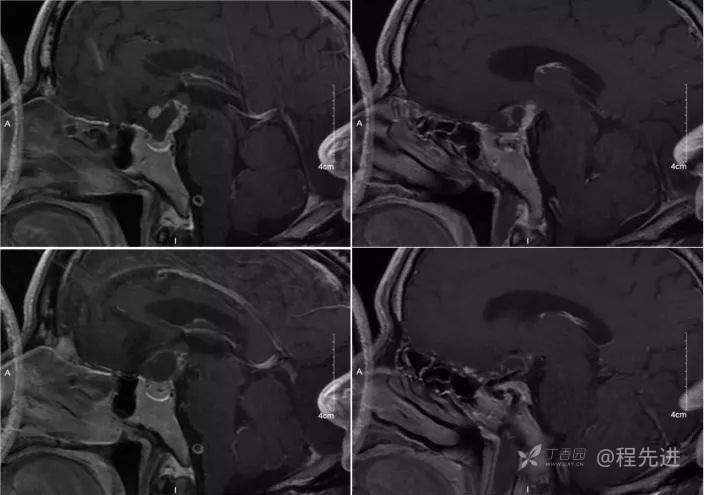

img

T1增强冠状位